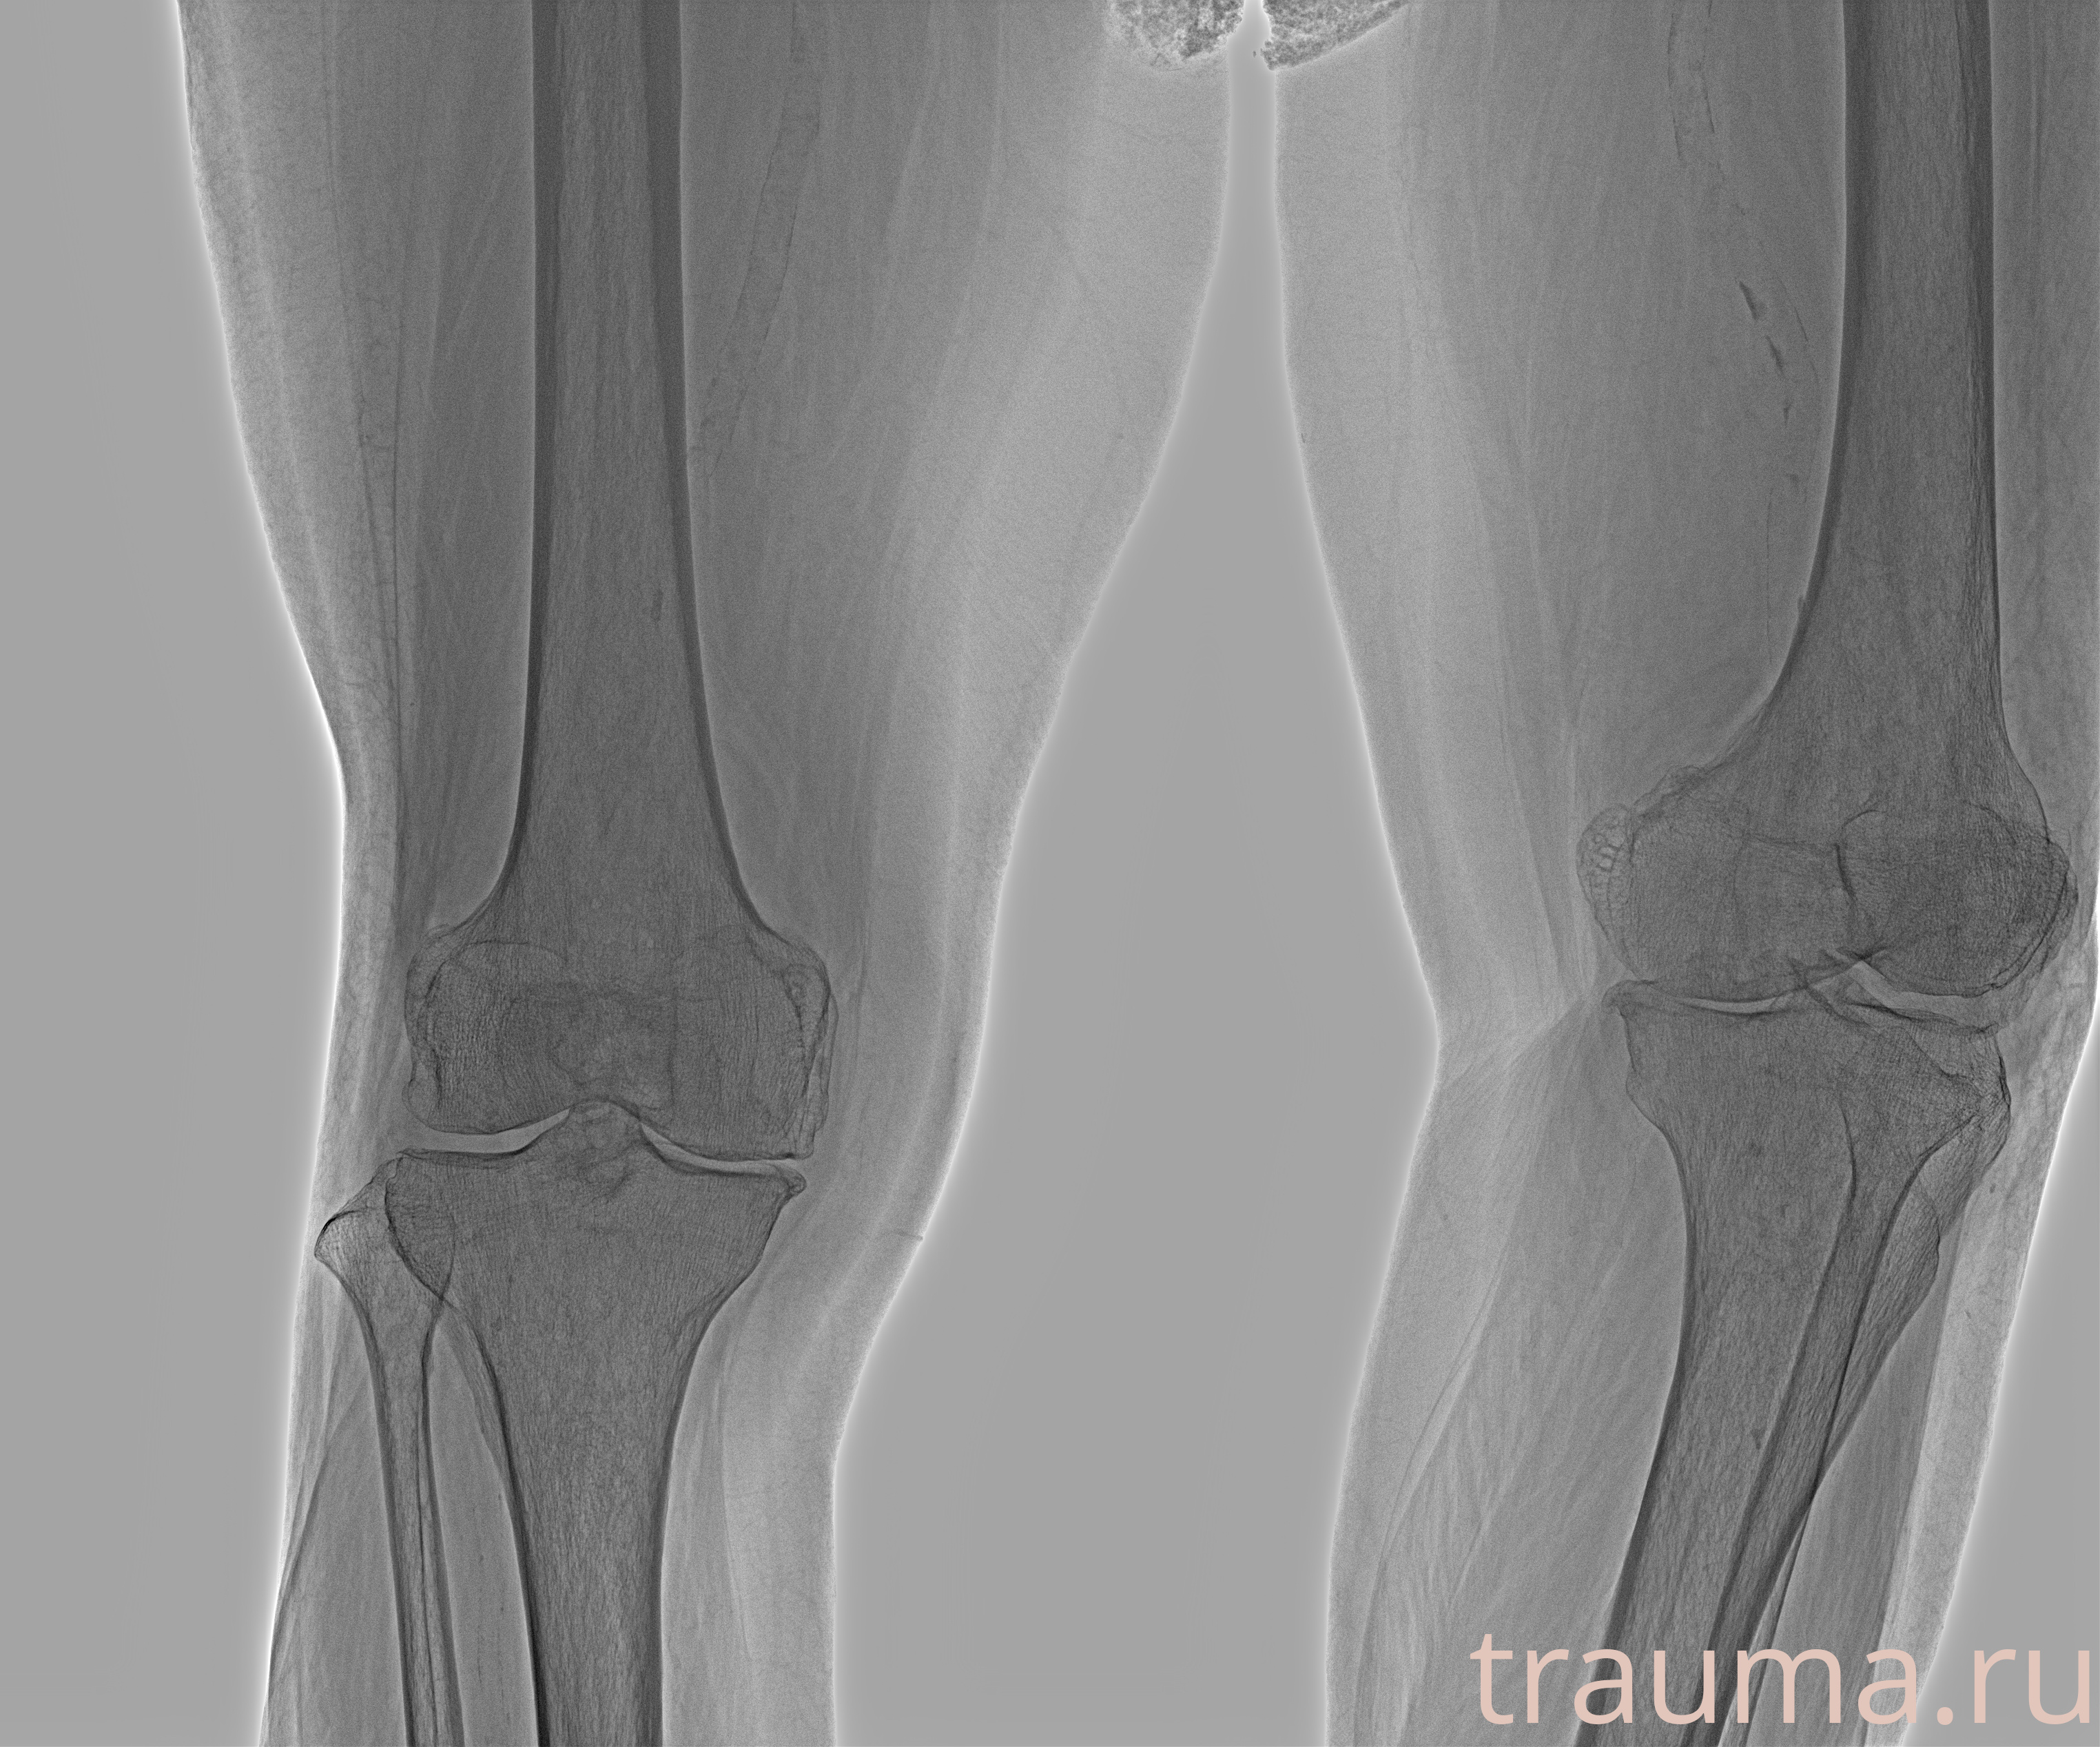

Рентгенограммы

Рентген на дому: по вашему адресу приезжает врач-рентгенолог, травматолог-ортопед с мобильным рентгеновским аппаратом, проводит диагностику травмы или заболевания, делает необходимые рентгенограммы, дает рекомендации по дальнейшему лечению. Получить качественные снимки в домашних условиях возможно благодаря уникальной методике, разработанной МосРентген Центром для института  Склифосовского